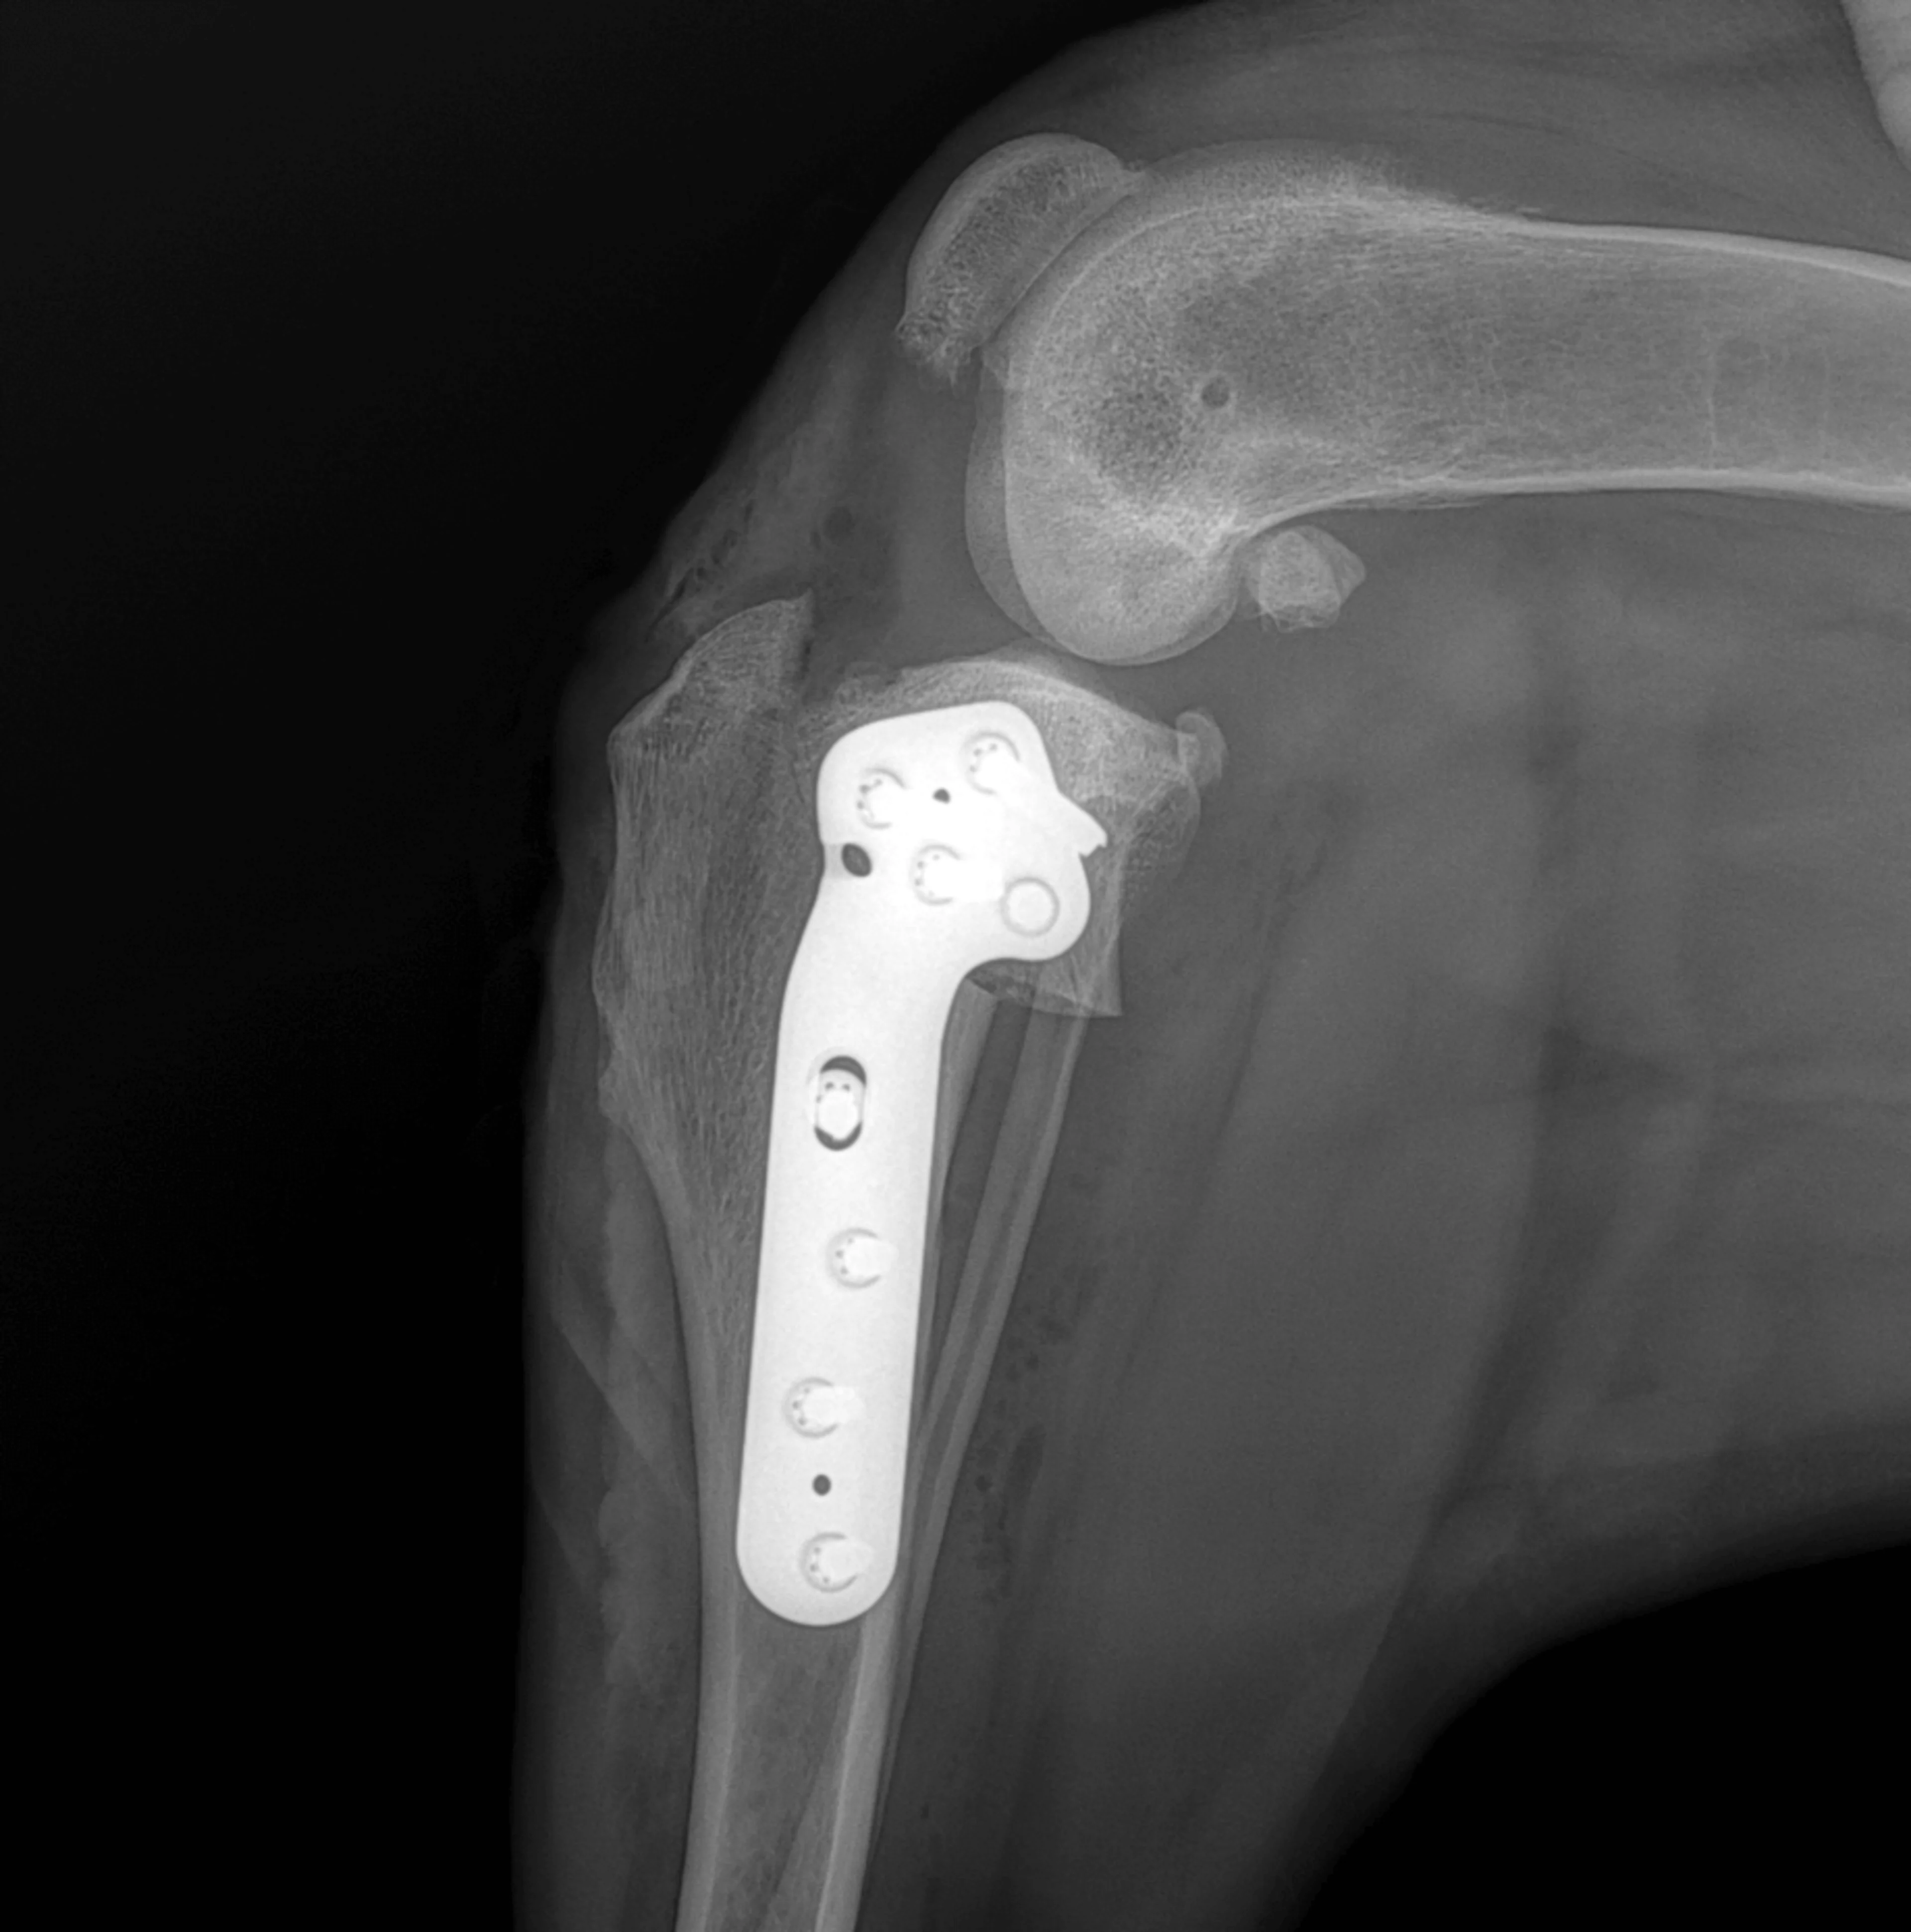

TPLO (Tibial Plateau Leveling Osteotomy): Hierbei wird die Schienbeinebene chirurgisch so verändert, dass die Belastungsachse des Kniegelenkes verändert wird. Dadurch wird die stabilisierende Funktion des vorderen Kreuzbandes neutralisiert, ohne dass es ersetzt werden muss. Durch die Zunahme an objektiven Studien in den letzten Jahren, hat sich herausgestellt, dass dies die einzige Methode ist, die das gleiche Belastungsniveau, wie am gesunden Bein gewährleistet. Diese Technik ist der internationale Goldstandard der Kreuzbandchirurgie beim Hund und eignet sich bei Hunden jeder Grösse.

Postoperative Röntgenaufnahme der TPLO-Technik. Zu sehen ist das rotierte Tibia Plateau, welches mit einer speziellen Platte fixiert ist.